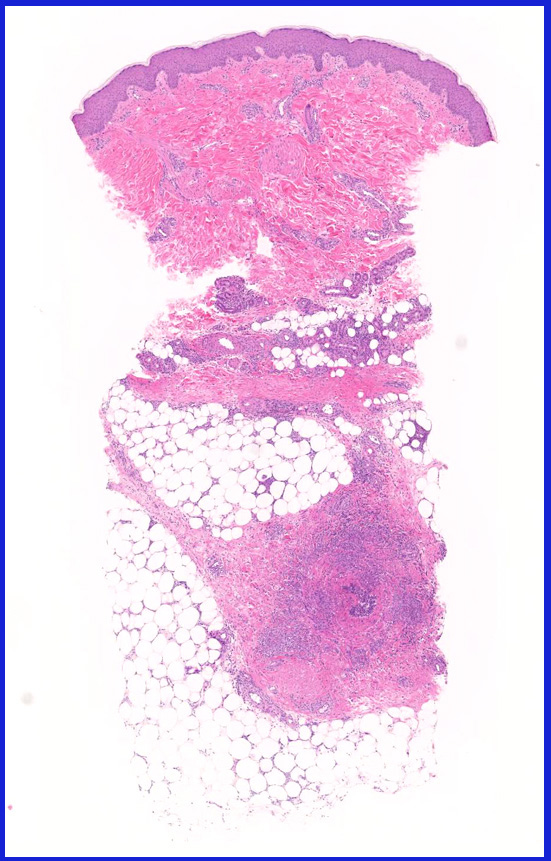

Behçet病が考えられた患者さんの下肢紅斑

30歳代後半男性

Behcetloupe.jpg

両側下腿に爪甲大から鶏卵大の圧痛を伴う紅斑が出現する。同時に陰嚢潰瘍、口腔内アフタも出現した。

皮膚の血管(静脈・細動脈)病変、脂肪織炎 (サムネイルをクリックすると大きな画像が見られます)